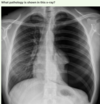

What pathology is shown in this chest x-ray?

Answer: Pulmonary oedema